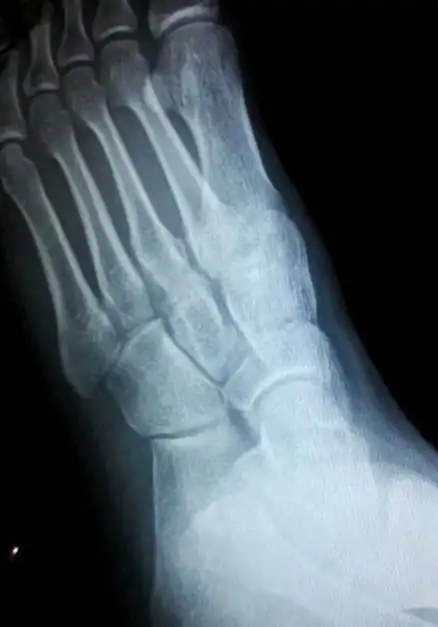

x 射线,脚,骨

脚掌骨折拆石膏后多久可以正常行走 2010-08-18 为什麽骨折的人石膏拿

第一跖趾关节也就是足大拇指与脚掌的第一跖骨形成的关节,为了方便筋

足骨骨折多久能好